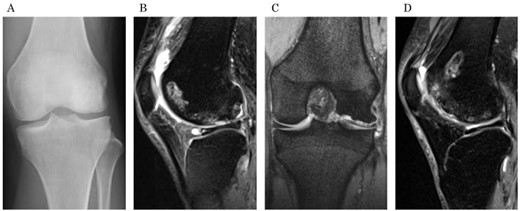

A 31-year-old female with SLE, who had been receiving oral steroid therapy since the age of 16, presented with severe pain in her left knee without any particular trigger. Physical examination showed local swelling and effusion in the left knee, and the passive ranges of motion for both extension and flexion were limited to −30° and 130°, respectively. Ligamentous instability or apparent malalignment was not noted. Radiographic examination of the knee showed flattened contour of the lateral femoral condyle and irregularity of the articular surface (Fig. 1a). MRI showed osteonecrosis extending from the lateral femoral condyle to the femoral trochlea, whereas a tear of the lateral discoid meniscus was also identified (Fig. 1b and c). A sagittal fat-saturated T2-weighted image of the contralateral right knee also showed osteonecrosis lesion in the lateral condyle (Fig. 1d). Based on those clinical and image findings, diagnoses of steroid-induced osteonecrosis of the femoral condyle and a tear of the lateral discoid meniscus were made. An urgent arthroscopy was performed as the patient was experiencing severe knee pain and limited extension of the knee because of detached osteochondral fragments and discoid meniscal tear. First, the ganglion connected to the anterior horn of the lateral discoid meniscus was resected, and a partial meniscectomy (meniscoplasty) was performed. A 35 × 45 mm cartilage defect was found in the lateral femoral condyle, and the detached osteochondral fragments were removed (Fig. 2a and b). After the removal of detached chondral lesions under arthroscopy, the limitation of the ROM and severe pain was resolved. However, a large osteonecrosis lesion with osteochondral defects remained, which presumably lead to secondary osteoarthritis. Therefore, OAT was planned as a second-stage surgery. At the OAT procedure, the contralateral knee could not be used for graft harvest because of the presence of osteonecrosis in the femoral condyle. Therefore, only two 10-mm diameter osteochondral grafts could be harvested from the non-weight bearing area of the medial femoral condyle in the ipsilateral knee, and then inserted into the recipient site (Fig. 3a and b). Since only part of the lesion area could be replaced by the host tissue, microfracture was performed in the remaining lesion. Postoperatively, ROM exercise was started immediately, whereas weight bearing was not permitted for the initial 4 weeks and gradually returned to full weight thereafter.

Preoperative radiographs and MRI. (a) An anteroposterior radiograph of the left knee shows the flattened lateral femoral condyle and irregular lateral joint surface. (b) A sagittal fat saturation T2-weighted image and (c) a coronal T2-weighted image show large osteonecrosis of the left lateral femoral condyle and lateral discoid meniscal tear associated with cyst formation. (d) A sagittal fat saturation T2-weighted image of right knee (contralateral knee) shows osteonecrosis of the lateral condyle similar to the left knee.